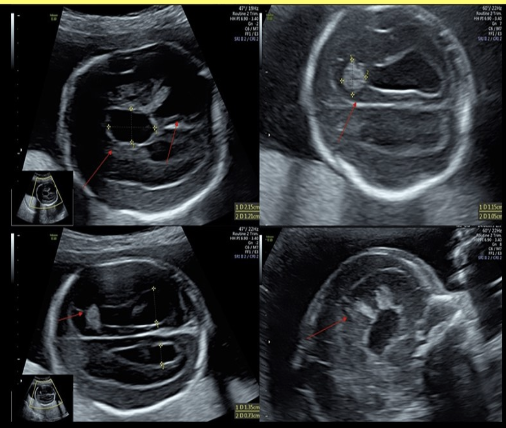

how is pulmonary sequestration differentiated from other chest masses

a) the only hyperechoic fetal chest mass

b) the only hypoechoic fetal chest mass

c) use color doppler to confirm there is no blood supply to the mass

d) use color doppler to identify the feeding artery from the AO